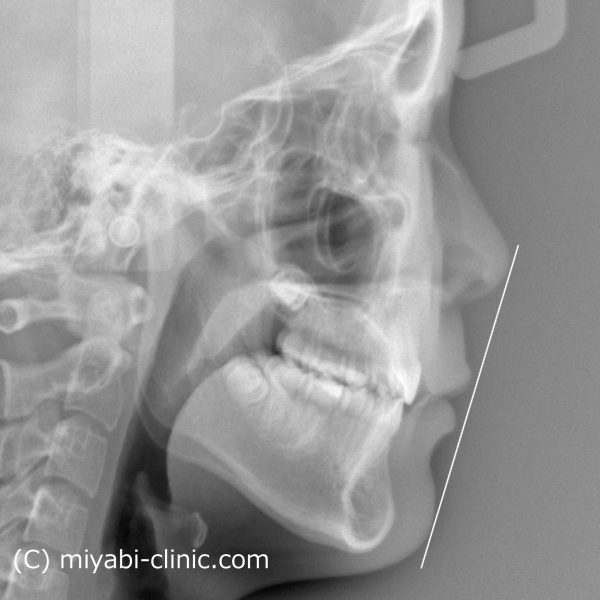

レントゲン写真を見てみると、

上下の歯が 前方に傾斜して、前に押し出されています。窮屈な状態ですね

E-ラインからも下口唇が出ています。